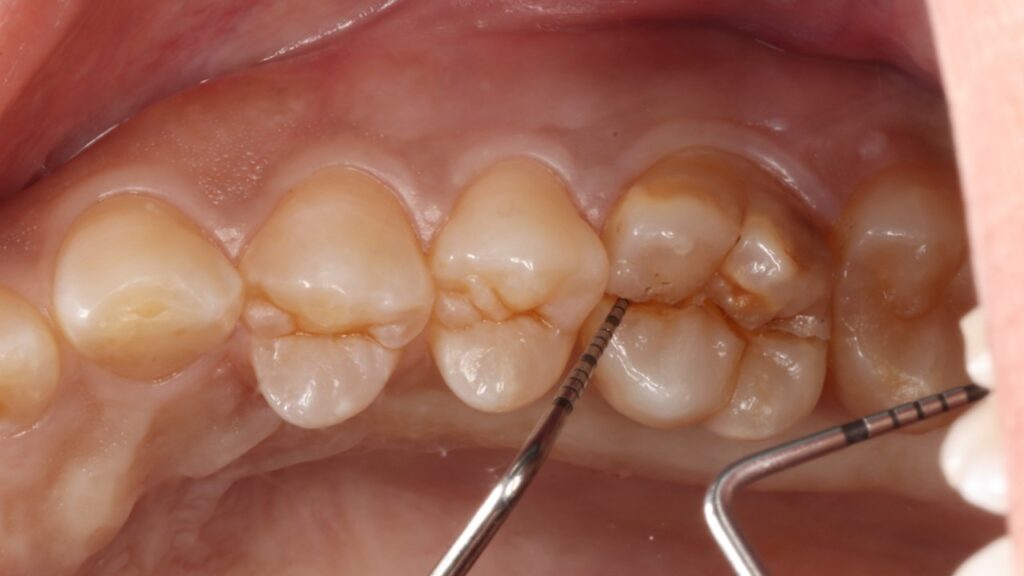

虫歯も歯周病もなく、一見何の問題もないように見えましたがマイクロスコープ(顕微鏡)で詳しく確認すると噛む力に歯が負けて真っ二つに割れてしまっていました。

このように健康な歯が真っ二つに割れることはめったにないのですが、こうなると神経に触る様な強い痛みが出ますし、CTスキャンをとると上顎洞炎にもなっていました。